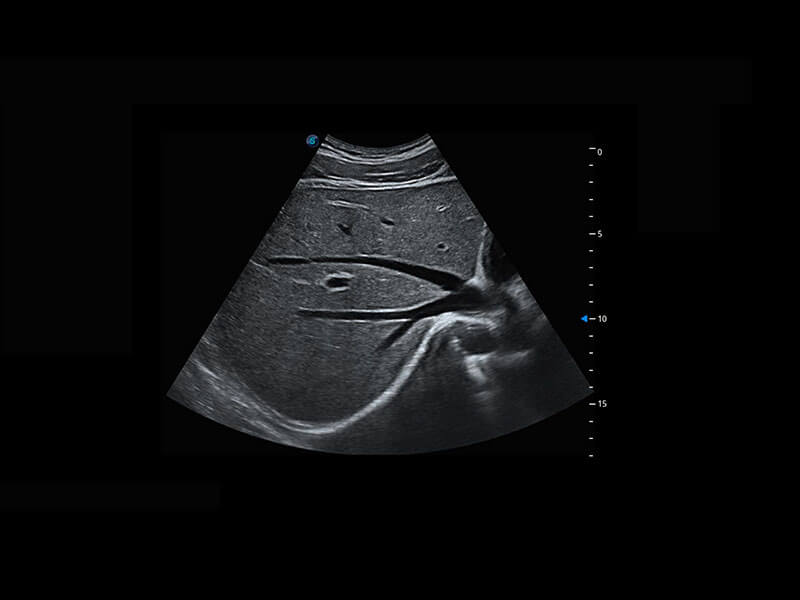

P60搭载一系列胎儿心脏成像技术,实现精细的胎儿心脏评估。

右室双出口